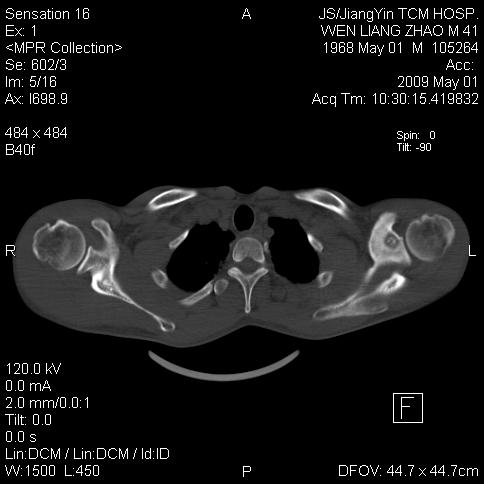

标题: CT19762:左侧喙突处压痛二年。考虑骨样骨瘤。 [打印本页]

标题: CT19762:左侧喙突处压痛二年。考虑骨样骨瘤。

左侧喙突处压痛二年。考虑骨样骨瘤。

病灶外缘膨胀明显,灶缘硬化较少,结合病史较符合骨母细胞瘤,其他亦不排除如软骨及软骨母细胞瘤等(病灶形态,成份较符合,发病部位也符合,只是年龄较大),骨样骨瘤多有较明显的自发性痛,且夜间痛明显,病史为压痛两年,不太符合.

多考虑内生性软骨瘤。年龄及发病部位及病史不支持骨样骨瘤。

支持骨样骨瘤(瘤巢小于1.5mm),骨母细胞瘤又称为巨大骨样骨瘤指瘤巢大于2cm的骨样骨瘤.

首先考虑内生软骨瘤,其次才考虑骨样骨瘤。